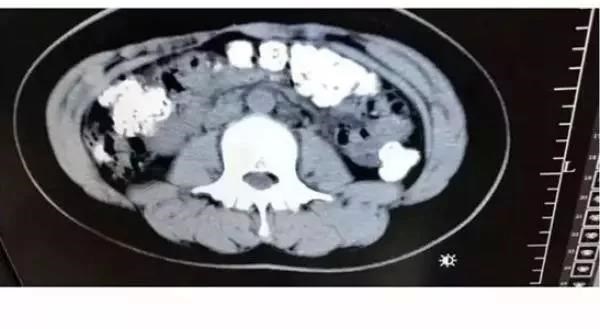

Các hạt trân châu chưa được tiêu hóa hết.

Phát hiện bụng cô bé phình to bất thường, các bác sỹ đã quyết định đưa bệnh nhân này đi chụp cắt lớp. Kết quả chụp cắt lớp cho thấy hàng trăm vật thể nhỏ hình tròn nằm trong khắp các cơ quan nội tạng, từ dạ dày, đại tràng, ruột và hậu môn.

Sau khi cùng nhau thảo luận, các bác sỹ kết luận những vật thể nhỏ này là các hạt trân châu chưa được tiêu hóa hết. Bác sỹ Zhang Louwei đã hỏi cô bé xem bệnh nhân có ăn gì khó tiêu trong vài ngày qua hay không. Cô bé thừa nhận đã uống một cốc trà sữa từ 5 ngày trước khi nhập viện.

Các hạt trân châu vẫn mắc kẹt trong hệ tiêu hóa.